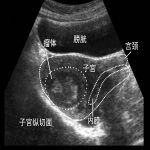

子宫腺肌症相关检查

子宫腺肌症常用的检查有:妇科检查、CA-125、CEA、AFP、激素六项、B超、3D腹腔镜(诊断治疗兼为一体),病理检查(术后)。根据腺肌症症状及临床表现、体征及相关检查可确诊。